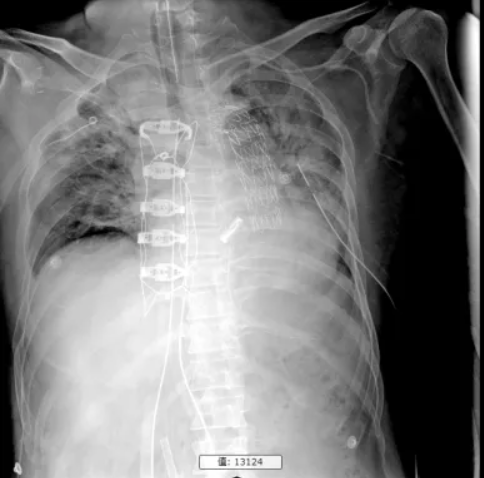

8天前,血常规示白细胞14.36*10^9/L,中性粒93.8%,PCT 40.5ng/ml,考虑感染加重,痰培养及外送血NGS示鲍曼不动杆菌(具体药敏不详);6天前调整抗生素为美罗培南1g q12h联合替加环素(泰阁)50mg q12h,12-18替加环素调整为100mg q12h。5天前,心包纵隔引流液由淡黄色变为血性引流液,伴鼻腔、穿刺部位渗血,停用比伐卢定,予氨甲环酸、纤维蛋白原、凝血因子、维生素K等止血治疗后好转。后复查胸片见肺部渗出较前加重,查白细胞及PCT明显升高,肾功能不全伴高钠血症,予CRRT治疗1次(因ECMO报警下机,12h)。1天前复查胸片渗出较前明显加重(图1),考虑病情危重,遂转至我科治疗。

图1.转运前胸片